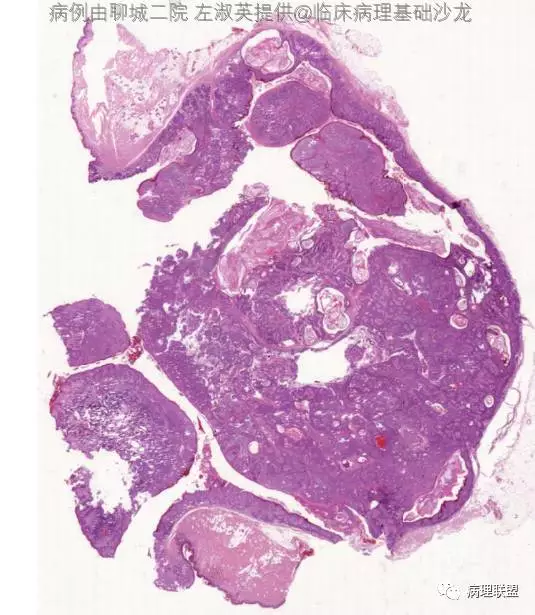

病例3

女,31,颈部肿物

图片信息

@左淑英 1毛囊瘤,2毛发上皮瘤。3是钙化上皮瘤。4是外毛根鞘瘤

四个病例,有点混乱了。3钙化上皮瘤。4增生性外毛根鞘瘤,2毛母细胞瘤,1分不清了毛囊分化,请左老师有时间讲解一下